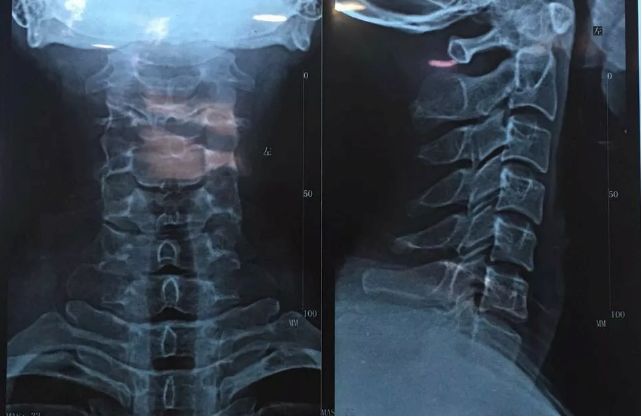

出现颈椎疼痛,手指麻木无力、头痛头晕等症状,是非常有必要到医院拍片子进行确诊的,明确病情的阶段和病情,才能做出针对性的治疗。